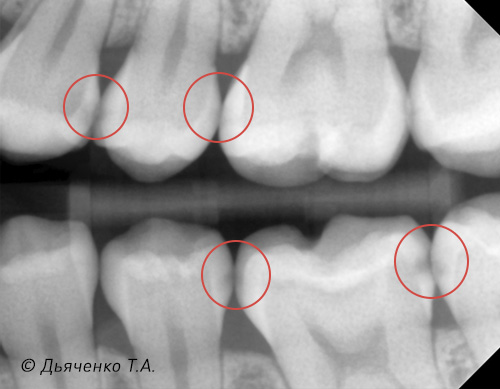

Также важна рентген-диагностика контактных пунктов Bite Wing (рис. 6 и 7). Это методика, когда, используя всего 2 рентгеновских (визиограф) снимка, мы можем просмотреть межзубные промежутки верхней и нижней челюсти с 2-х сторон.

Очень часто, особенно у подростков, ввиду низкой минерализации зубов, обнаруживается множество скрытых кариозных процессов между зубами на рентгеновских снимках.

Как видно на рис. 7, межзубные полости могут быть разного размера: